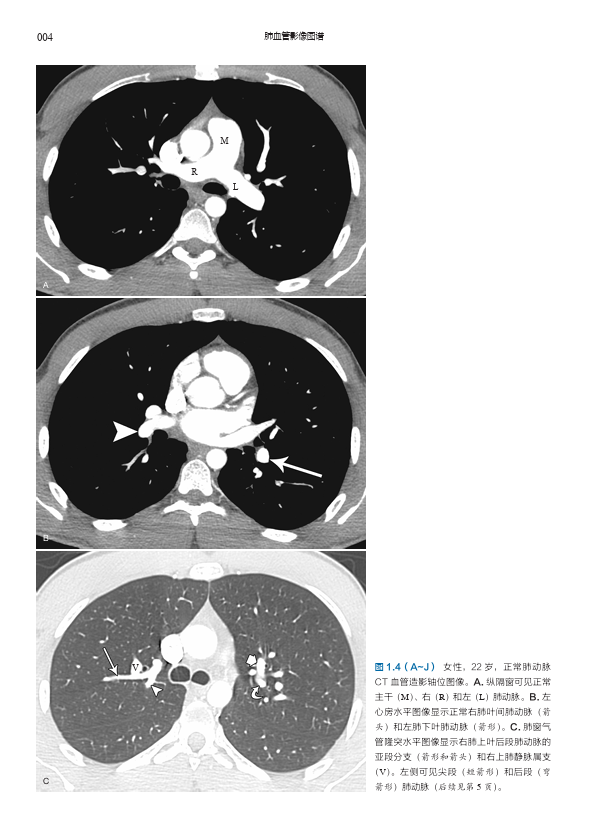

本书是由哈佛大学医学院附属麻省总医院 Conrad Wittram 编写的有关肺血管疾病的综合影像图谱,内容包括肺血管正常解剖、先天性肺部疾病和心脏疾病的肺血管变化、特定类别的肺血管疾病(如栓塞、血栓形成、血管炎、动脉瘤和静脉瘤、感染、肿瘤、肺高血压等)、创伤与介入治疗相关肺血管问题,以及全身和肺部疾病的肺血管变化的影像学表现及特点。本书内容翔实,编排简明清晰,图文配合,每一页上都有详细的、清晰标记的高质量影像图,展示了 X 线片、血管造影、多层螺旋 CT、MRI、超声和核素显像等多种成像方式下的影像表现,配以绘图及指示性箭头等,使得影像特征更加清晰;文字精要,突出了最相关的重要信息。

肺动脉 001